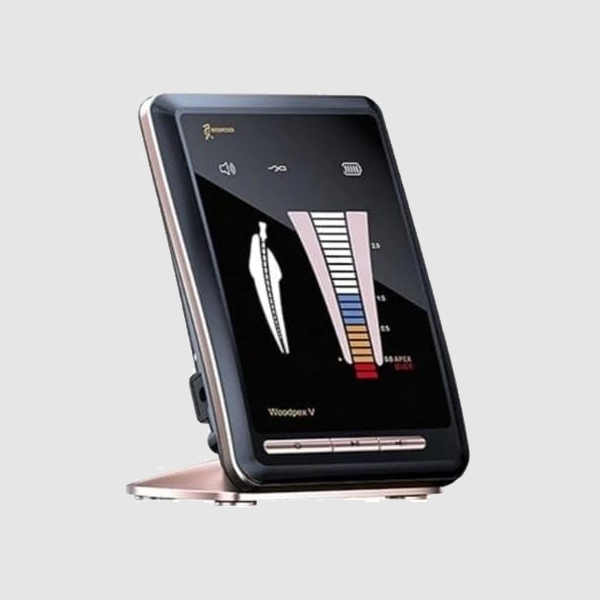

Realizamos siempre la endodoncia con las normas de seguridad vigentes, con Localizador Apical que nos va a orientar en la ubicación de la lima en el canal radicular, y siempre utilizamos aislamiento absoluto del campo operatorio.